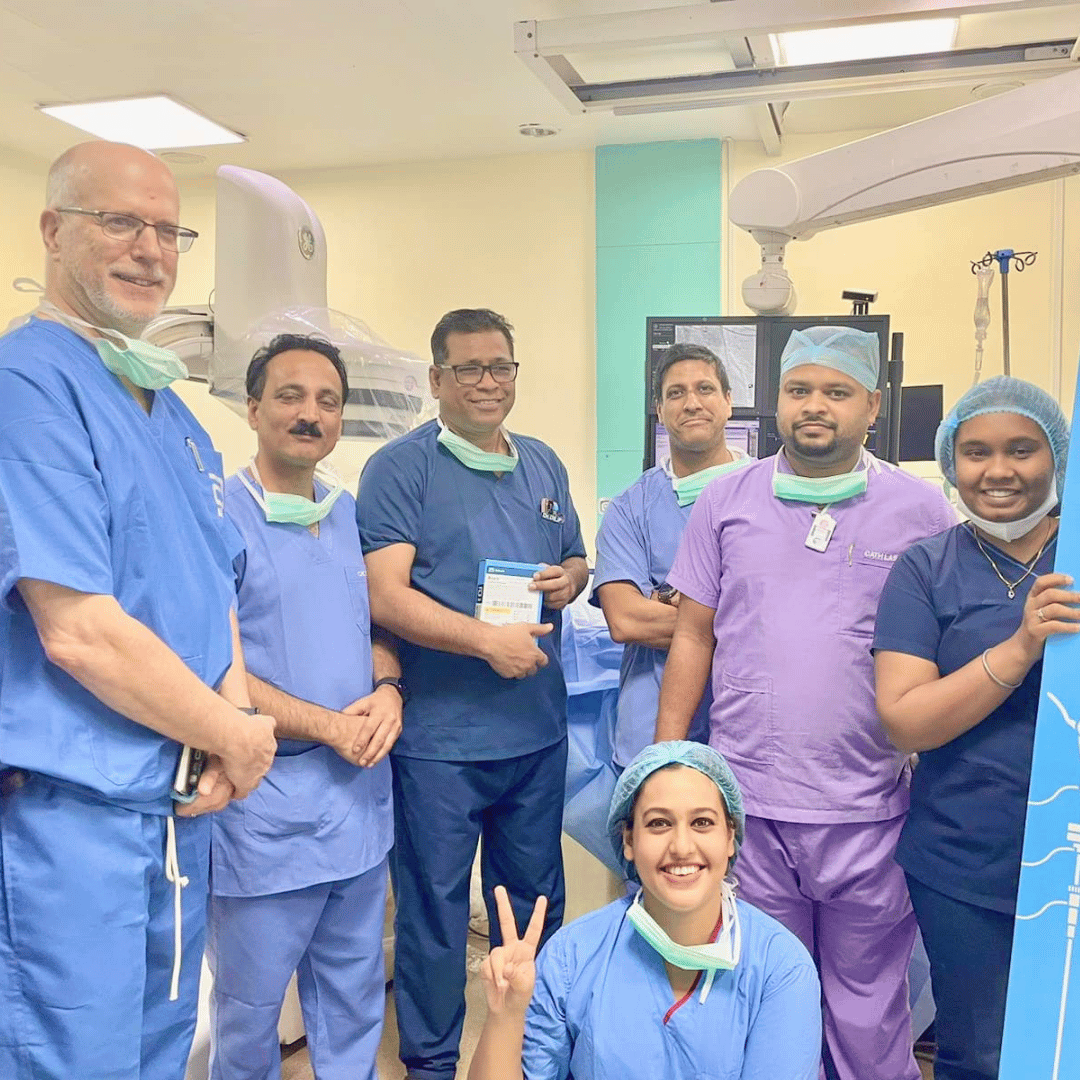

Dr. Dilip Kumar Leads the Way with Eastern India's First Aveir Leadless Pacing Capsule Cases at Medica

Milestone Achieved: First Micra AV Procedure in Jharkhand at Medica Ranchi